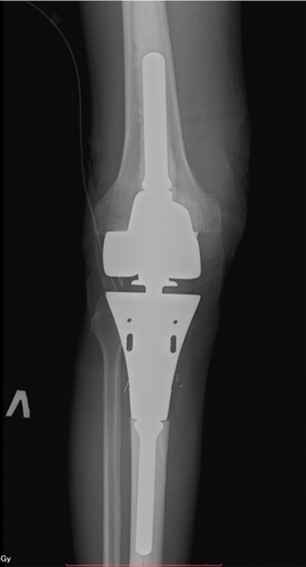

Рентгенограмма после эндопротезирования

Рентгенограмма после эндопротезирования проксимальной трети большеберцовой кости и коленного сустава